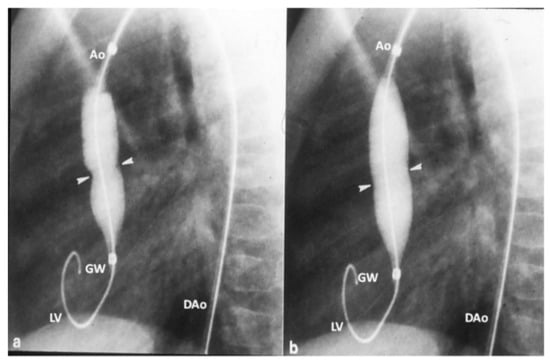

- Rao, P.S. Balloon angioplasty of native aortic coarctation. In Transcatheter Therapy in Pediatric Cardiology; Rao, P.S., Ed.; Wiley-Liss: New York, NY, USA, 1993; pp. 153–196. [Google Scholar]

- Rao, P.S. Coarctation of the aorta. Curr. Cardiol. Rep. 2005, 7, 425–434. [Google Scholar] [CrossRef]

- Doshi, A.R.; Rao, P.S. Coarctation of aorta—Management options and decision making. Pediatr. Ther. 2012, 5, 006. [Google Scholar] [CrossRef]

- Rao, P.S. Should balloon angioplasty be used as a treatment of choice for native aortic coarctations? J. Invasive Cardiol. 1996, 8, 301–313. [Google Scholar] [PubMed]